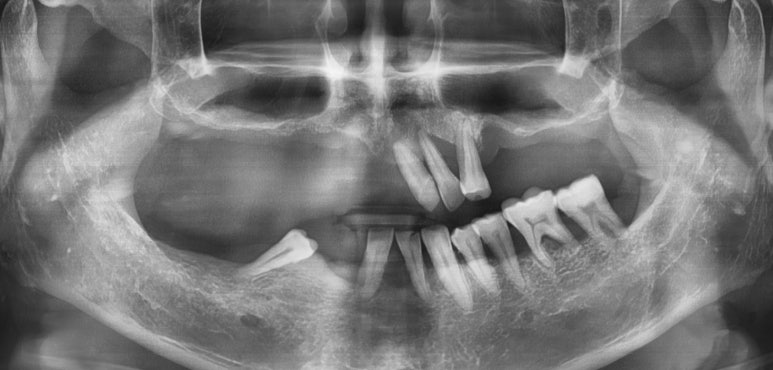

- 기초 수급자 환자 흔들리는 위 치아 빼고 위 전체 틀니,

아래쪽 어금니는 씹을 수 있게 최소 개수의 임플란트

- 상악 전체임플란트, 하악어금니 없는 부분 임플란트

상악 흔들리는 브릿지와 치아 발치 후 상악전체 임플란트

↓

상악 전체 임플란트 후

- 상악 전체임플란트 및 하악 어금니 없는 부위 임플란트